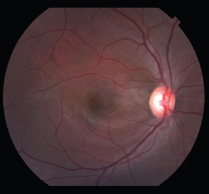

At six month follow up, the patient s visual acuity had returned to 20/20 with complete resolution of the intraretinal lesions. However, he complained of a persistent para central scotoma which was demonstrated using Amsler grid, and confirmed with 10-2 Humphrey Visual Field. OCT of the right eye showed a small area of sub foveal RPE irregularity despite resolution of the macular edema.

Figure 1C: Fundus photo of the right eye at 6 month follow up showing complete resolution.